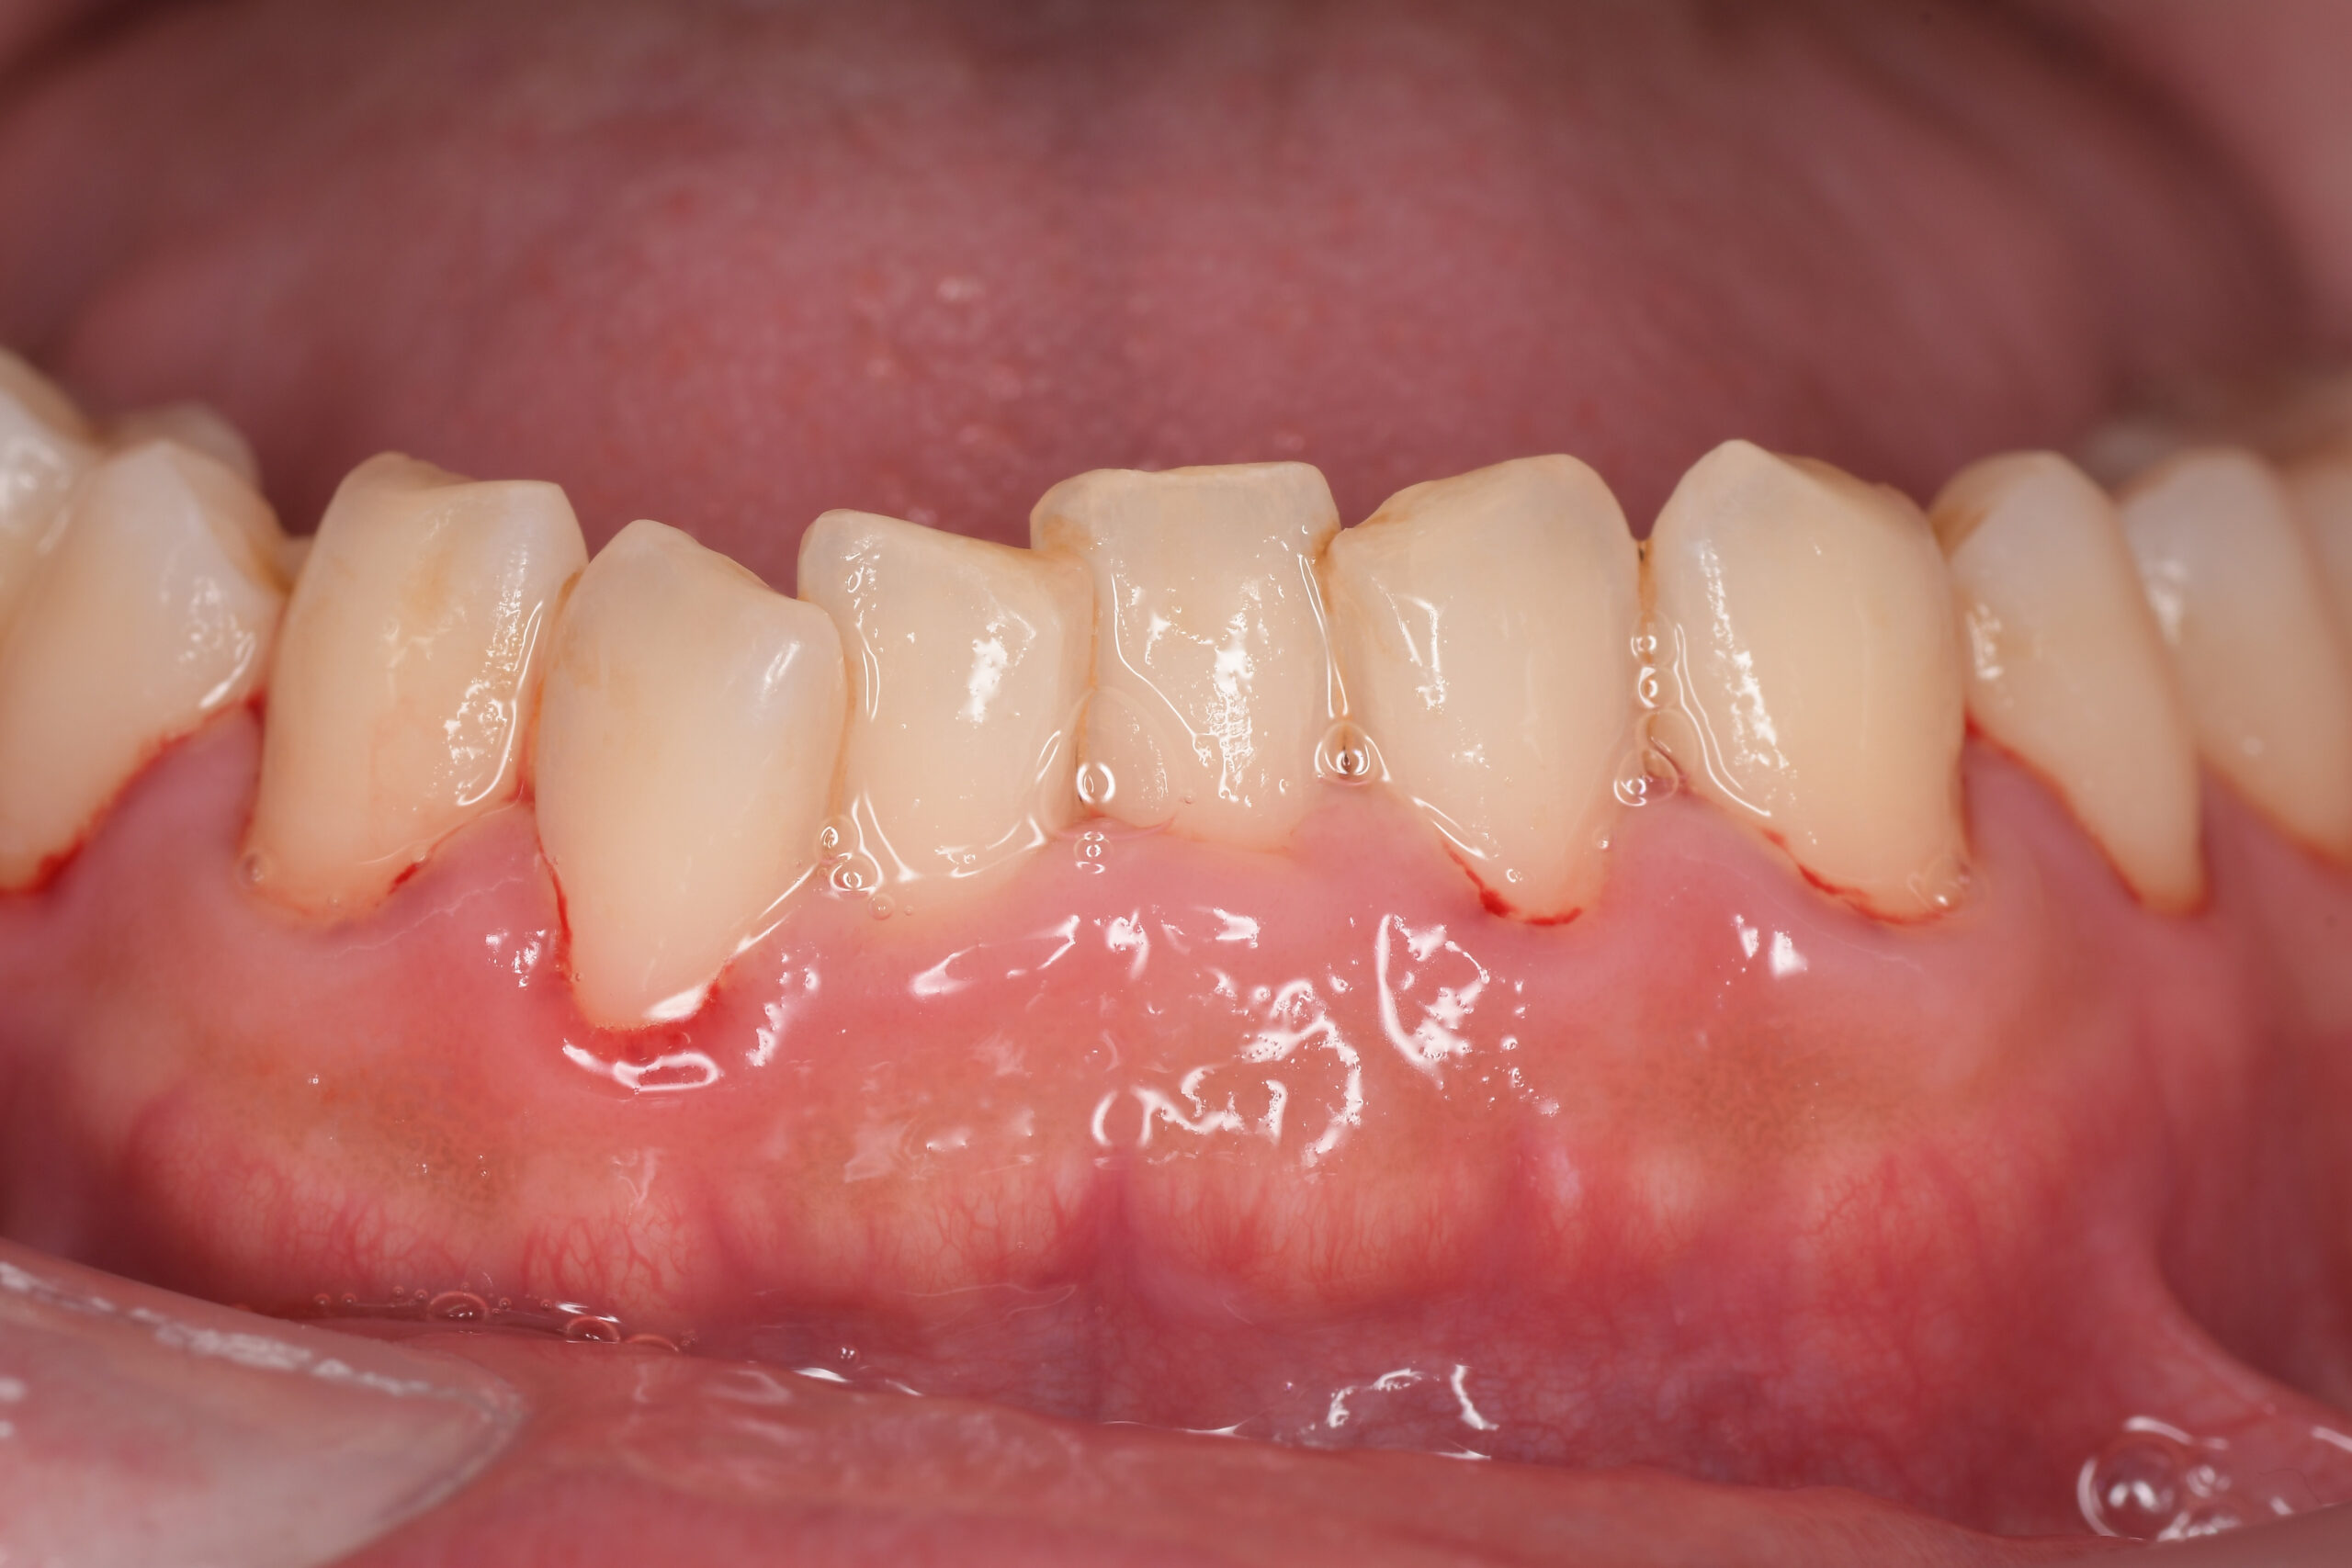

CASE 10

Before①

After①

Before②

After②

基本情報

| 年齢・性別 | 38歳・男性 |

|---|---|

| 主訴 | 下顎 歯石除去したい |

| 治療内容 | スケーリング |

| 治療期間 | 30分 |

| 治療費 | 約1,500円(保険診療) |

| リスク・副作用 | 知覚過敏、歯肉退縮 |

| 治療方針 | 歯肉縁上歯石を除去してから歯肉縁下歯石を除去します。ご自身でのプラークコントロールができるようになったら定期検診に移行します。 |

| 担当者所見 | 半年ぶりの歯科医院の受診。歯石が付きやすいためセルフケアの重要性をお伝えして、定期的にクリーニングを行います。出血率が高く炎症が強いため、今後はセルフケアを強化して歯周病治療を行います。 |